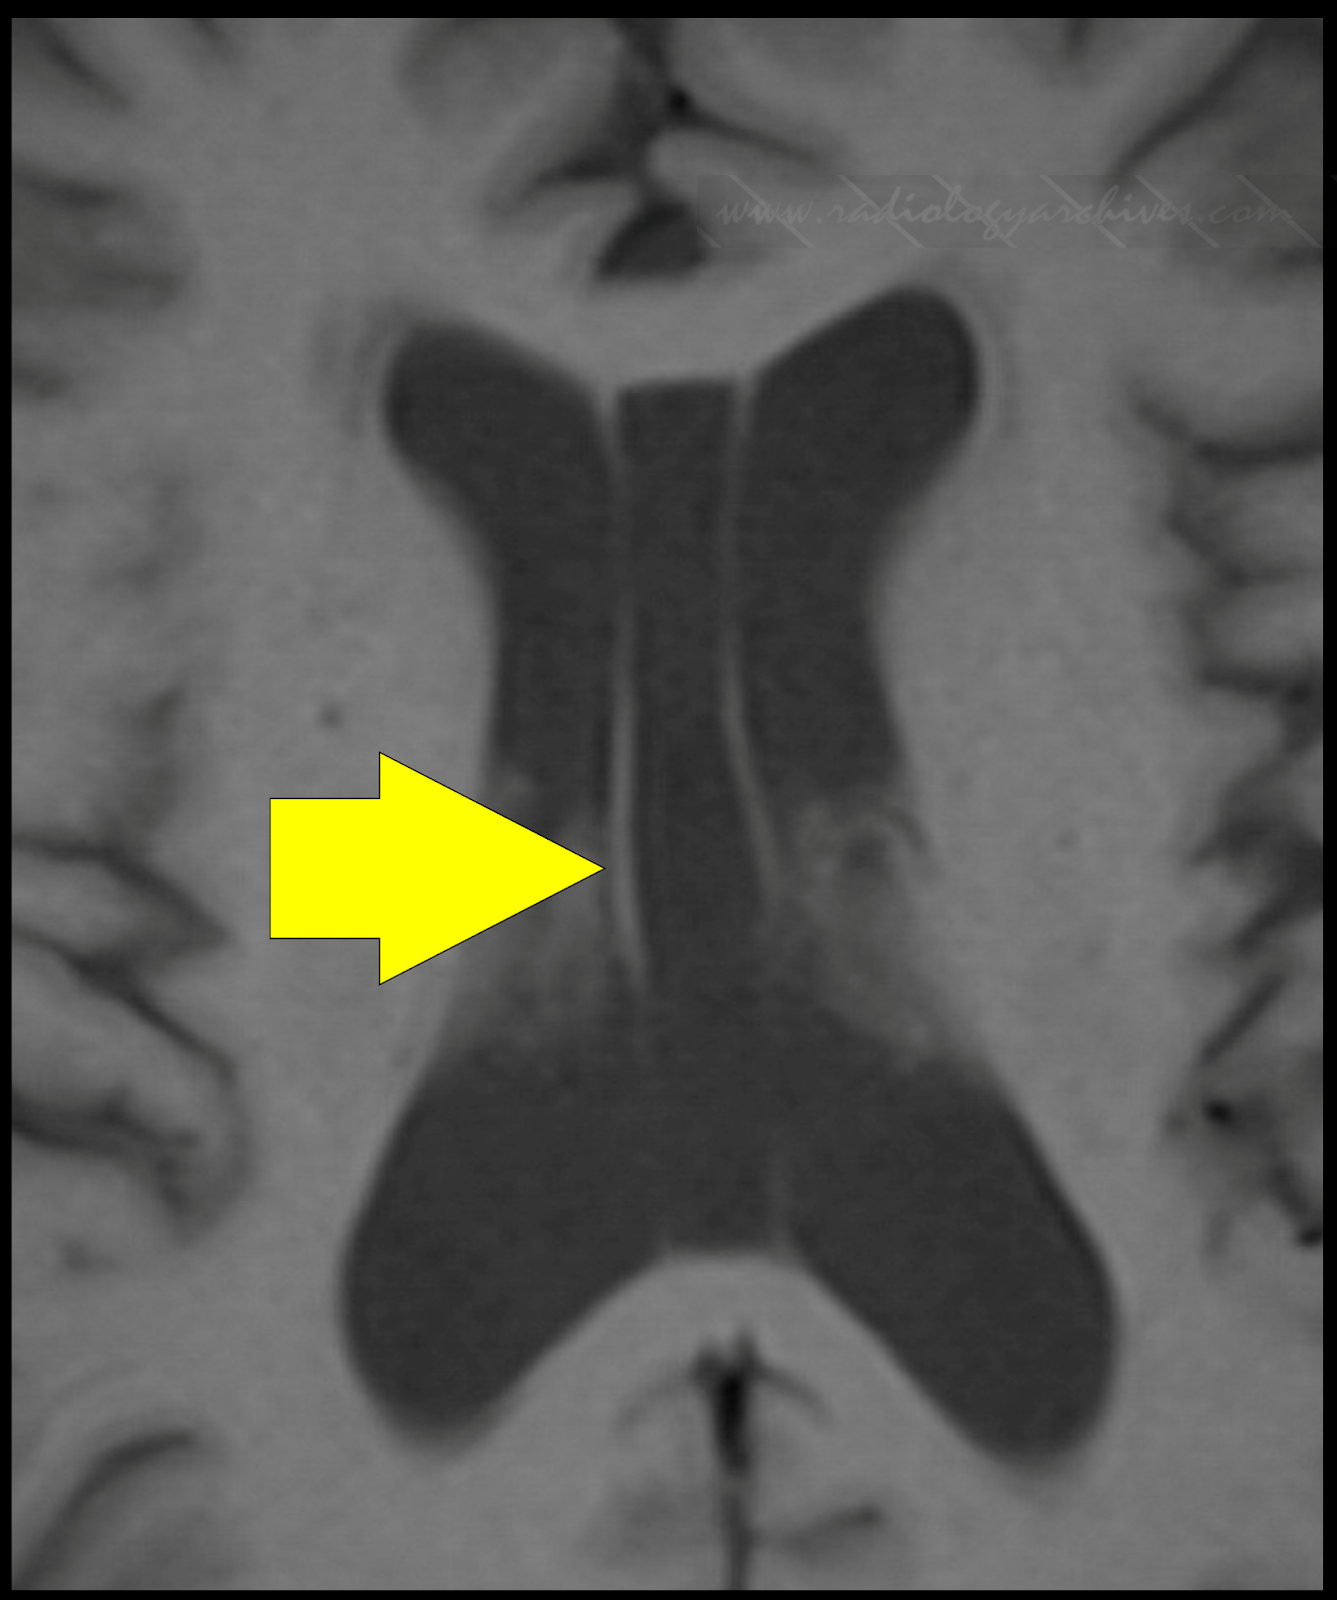

Presented case illustrated in coronal section CSP Cavum septum

From www.radiologyarchives.com

Radiology Archives Cavum Vergae Cavum Velum Interpositum Vergae There may also be a space above the velum interpositum between the hippocampal commissure and splenium called the cavum. It is superior to the columns of the fornices, which are displaced inferiorly. Cavum veli interpositi is usually an incidental finding at an mri or ct scan and is mostly asymptomatic (see images. The third related intracranial midline cyst is a. Cavum Velum Interpositum Vergae.